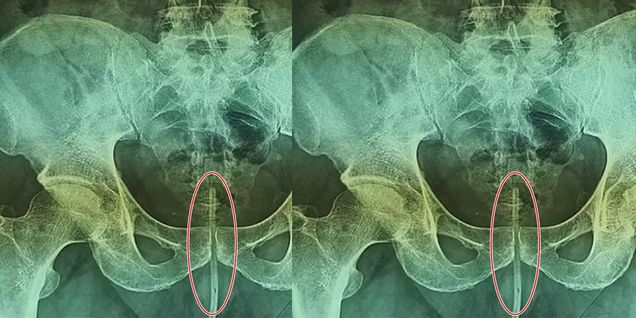

न्यूज़: पाकिस्तान से एक बेहद हैरान करने वाला मामला सामने आया है जहां डॉक्टरों की एक टीम ने एक शख्स के प्राइवेट पार्ट से इलेक्ट्रिक केबल निकाली है। यह सब तब हुआ जब उस शख्स ने जानबूझकर इस 18 सेंटीमीटर केबल को अपने प्राइवेट पार्ट में डाल लिया था। बताया गया कि शख्स ने ऐसा इसलिए किया क्योंकि उसे कुछ समय से पेशाब करने में दिक्क्त महसूस हो रही थी। दरअसल, यह घटना पाकिस्तान के कराची की है। डेली मेल की एक रिपोर्ट के मुताबिक इस शख्स के नाम को गोपनीय रखा गया है, शख्स को कुछ समय से पेशाब की समस्या थी। इसी को ठीक करने के लिए उसने 18 सेंटीमीटर लंबे तार को अपने मूत्रमार्ग में डाल लिया, लेकिन वह अंदर जाकर फंस गया। इस घटना के बाद शख्स को कराची के अस्पताल में भर्ती कराया गया।

इस शख्स को जब दर्द हुआ तो वह डॉक्टरों के पास पहुंचा। वहां पर उसकी जांच की गई और एक्सरे करवाया गया। डॉक्टरों ने देखा कि उसके प्राइवेट पार्ट में कुछ फंसा हुआ है। जब डॉक्टरों ने एक्सरे देखा तो उनके होश उड़ गए। फिलहाल तत्काल शख्स की सर्जरी करके इसे निकाला गया। डॉक्टरों की टीम ने बताया कि इससे शख्स की मौत भी हो सकती थी। यह अपने तरह का ऐसा पहले मामला नहीं है कि किसी शख्स ने ऐसा काम किया हो। कुछ समय पहले ब्राजील से एक ऐसा ही मामला आया था जब जहां डॉक्टरों की एक टीम ने एक शख्स के प्राइवेट पार्ट से एक्सरसाइज करने वाला एक डंबल निकाला था। उस शख्स ने जानबूझकर इस दो किलो के डंबल को अपने प्राइवेट पार्ट में डाल लिया था। बताया गया कि शख्स ने सेक्शुअल प्लीजर के लिए ऐसा किया था।